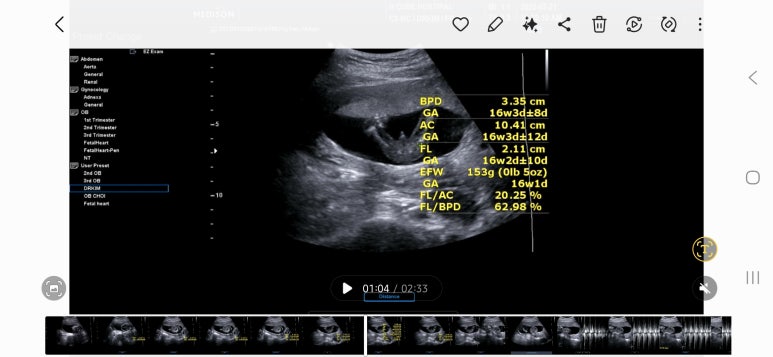

이제 예전하고는 다르게 굉장히 재는게 많아요!

16주부터는 아기 키를 재는게 의미가 없다고 합니다.

그래서 아기 머리 크기(지름), 아기 복부 둘레, 허벅지 길이? 를 재고

요걸로 아기 무게를 추정해서 알려줘요!

16주 아기는 이렇게 척추도 도로로로로 이어져있고 저 중간에 검은 부분은 심장이에요!

일단 16주 평균대로 잘크고 있다는 소견을 받았습니다^^